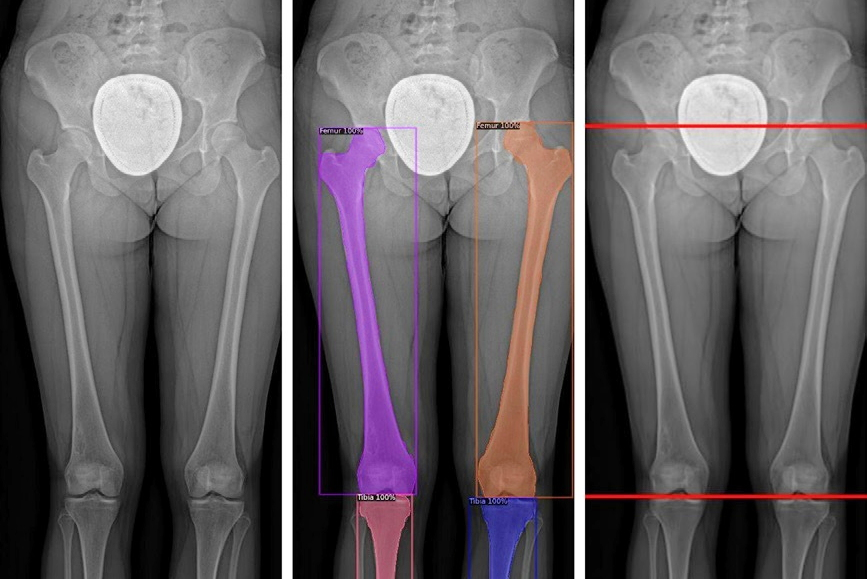

They analyzed these images, as well as demographic and surgical features associated with to identify the 11 most predictive features of subsequent AVBT corrections and trained a gradient boosting regressor (GBR) model to predict outcomes based on these features. The dataset (for all patients) was randomly split into training (80%) and testing (20%) datasets.